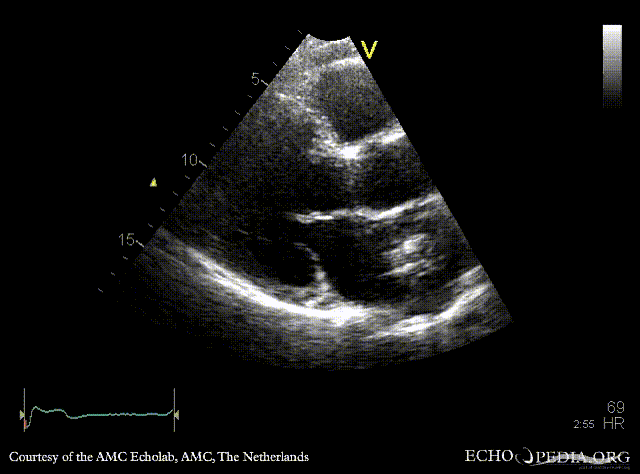

| A4CH | A2CH |